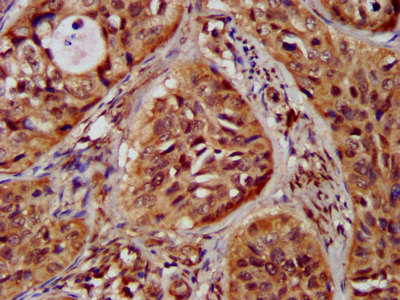

IHC image of CSB-PA612121LA01HU diluted at 1:300 and staining in paraffin-embedded human cervical cancer performed on a Leica BondTM system. After dewaxing and hydration, antigen retrieval was mediated by high pressure in a citrate buffer (pH 6.0). Section was blocked with 10% normal goat serum 30min at RT. Then primary antibody (1% BSA) was incubated at 4°C overnight. The primary is detected by a biotinylated secondary antibody and visualized using an HRP conjugated SP system.